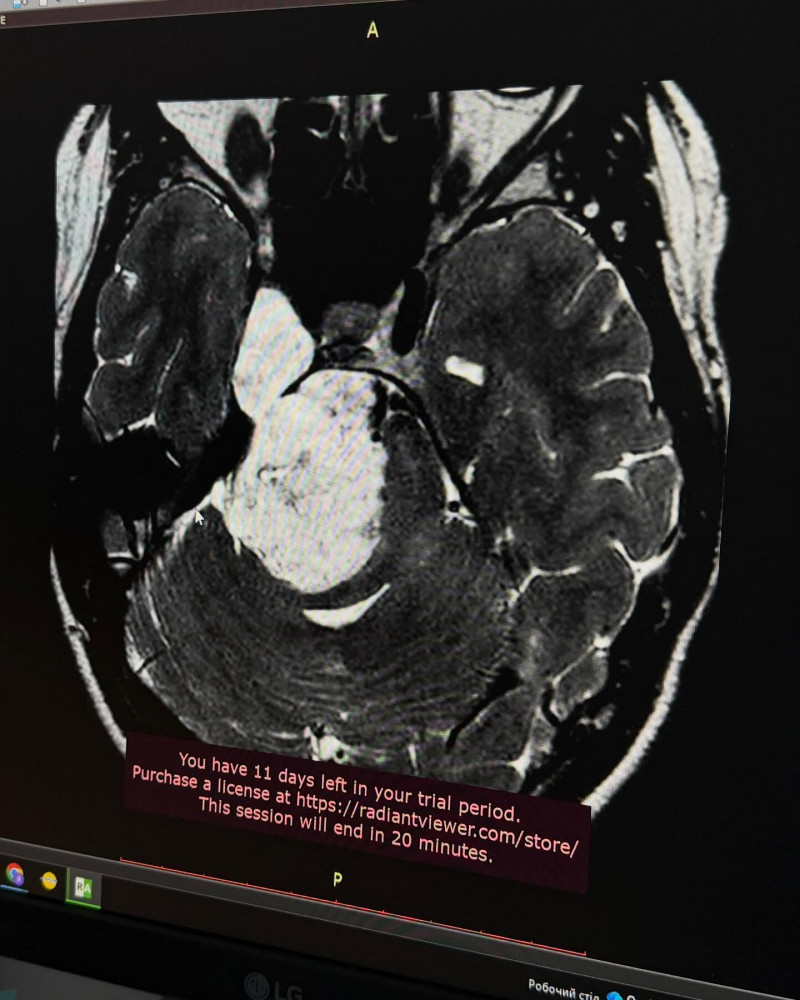

Польські спеціалісти провели МРТ і виявили велику пухлину головного мозку.

Дівчина довірилася львівським нейрохірургам Лікарні Святого Пантелеймона. Виявилося, що у мозку пацієнтки розрослася холестеатома — доброякісне новоутворення, яке виросло до 6×3 см, поширилося на дві черепні ямки та вже стискало стовбур мозку. Це й пояснювало проблеми зі слухом, зором і координацією та становило пряму небезпеку для життя.